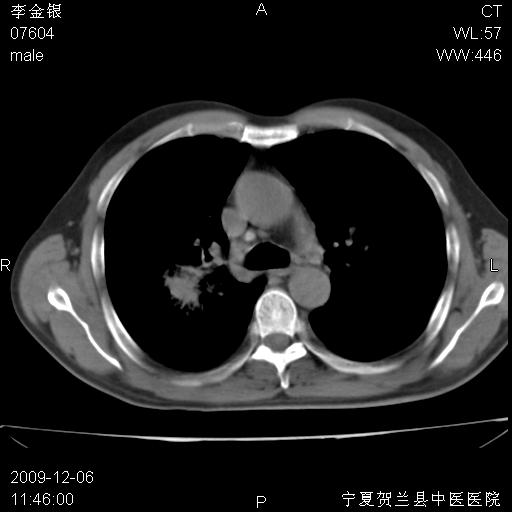

该病人 ,男,62岁,主因咳痰带血两天

考虑右肺中心型肺癌伴阻塞性肺炎及右肺门淋巴结转移,建议纤维支气管镜进一步检查。

支气管壁明显增厚 管腔狭窄,腔静脉后多个淋巴肿大,结合年龄病史考虑右肺上叶中央型肺癌并阻塞性肺炎

右肺上叶后段支气管阻塞,右上肺门占位,相应肺段阻塞性肺炎,右肺门有淋巴结肿大。诊断右肺上叶中心型肺癌,阻塞性肺肺炎、右肺门淋巴结转移。

符合中央型肺癌的ct表现并肺出血。但有一点腔静脉后有一钙化的淋巴结啊

右肺中心型肺癌伴阻塞性肺炎及右肺门与纵膈淋巴结转移很典型,可纤维支气管镜进一步检查

考虑右侧中央型肺癌伴右肺上叶后段阻塞性炎症、肺不张、右肺门和纵隔淋巴结肿大。

右肺上叶中心型肺癌,阻塞性肺炎、右肺门和纵隔淋巴结转移。